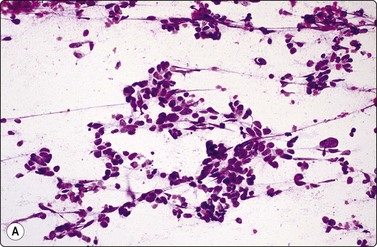

Small cell carcinoma (Figs 8.25-8.29)32,35,36,79,82,83

image

Fig. 8.25 Small cell carcinoma

Loose clusters with some dispersal and smearing artifact (Pap, HP).

Fig. 8.26 Small cell carcinoma

Pleomorphic poorly cohesive cells with little or no cytoplasm; nuclear molding (MGG, HP).

Fig. 8.27 Small cell carcinoma

Small loose cluster showing absence of cytoplasm, finely granular chromatin, inconspicuous nucleoli, nuclear molding and teardrop cells (H&E, HP).

Cytology is very successful in diagnosing small cell carcinoma in sputum and pleural fluid; in fact, sputum cytology may be more accurate than FNAC in typing this lesion. The criteria for the diagnosis of small cell carcinoma in aspirated material are similar to those in other sample types, but there are some important differences.

Cell pleomorphism is so distinctive that a diagnosis of malignancy is seldom in doubt (Figs 8.25-8.27). The most immediate impression is the absence or sparseness of cytoplasm rather than the small size of the neoplastic cell (Figs. 8.26 and 8.27). In fact, the cell nuclei may appear larger than similar cells in sputum and this may mislead one into making a diagnosis of non-small cell carcinoma. This difference in size between sputum and aspirated material is due to degenerative changes and shrinkage in sputum. It is sparseness of cytoplasm rather than size which is the most helpful initial clue in differentiating the lesion from other pulmonary carcinomas.

The combination of dispersal with clustering is also important, especially when other small cell neoplasms enter the differential diagnosis (Fig. 8.25). Lymphomas generally do not display such cell cohesion, although large fragments may be dislodged, and in some cases lymphoid cells may form clusters or packets.

Fragility of nuclei is emphasized by tear-drop cells or streaks of smeared nuclear material,226 and the close nuclear apposition and molding so commonly seen in sputum are also evident (Figs 8.26 and 8.27). Uniform coarsely granular ‘salt and pepper’ nuclear chromatin is also a well-recognized feature of this cancer in other sites, but one point of difference from sputum is the frequency of small nucleoli in aspirated material; they are less commonly seen in sputum. This may also be related to the better preservation of cells removed directly from tumor; small nucleoli are also often seen in bronchial brush material. Mitotic figures are usually easily found.